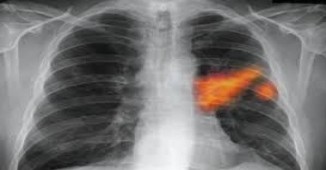

სამწუხაროდ, პაციენტების უმრავლესობა ფილტვების სიმსივნის შესახებ მხოლოდ გვიან სტადიაზე იგებს, რადგან ამ საშინელი, მომაკვდინებელი დაავადებისთვის საწყის..